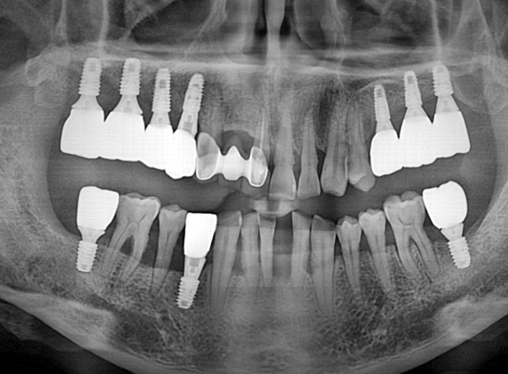

상악동 거상술을 동반한 상하악 임플란트 증례

After

너무 치조골 흡수가 많이 진행되어서 임플란트가 어려울 것 같은 부위에도

다행히 골생성이 잘 되어서 보철까지 마무리가 잘 된 케이스 입니다.